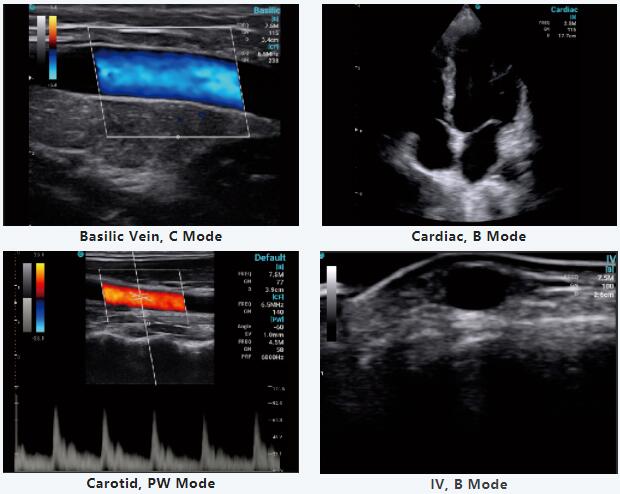

在这次特别的网络研讨会上,Jerome博士分享了他使用zoty中欧体育全站 SonoEye的部分日常工作,通过他的视频,中欧体育中国对SonoEye的便携性和精确的诊断印象深刻,并发现SonoEye在临床应用中的帮助有多大。

此外,Jerome博士还分享了SonoEye的创新功能,并对手持超声市场做出了全面、有价值的分析。手持式超声波的重要性和需求将继续增加,使优质医疗保健触手可及。